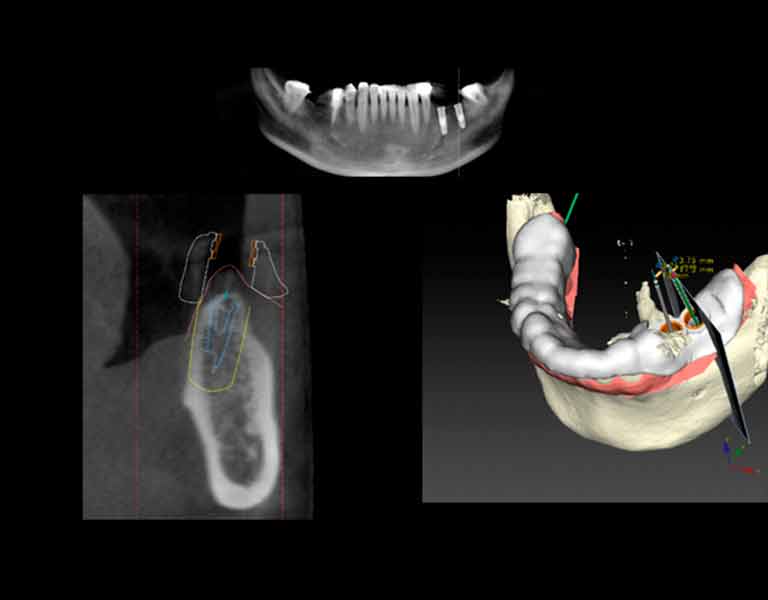

抜歯即時埋入インプラント

抜歯と同時にインプラントを埋め込む方法で負担を軽く、早く噛める!

かつては難しいテクニックとされてきましたが、近年、インプラント製品の改良、そしてインプラント技術の向上により、治療の確実性が高まりました。とは言え、高度なテクニックを必要とするため、どこの歯科医院でも行っているわけではありません。当院では、安全性に問題がない場合には積極的に抜歯即時埋入インプラントを行っています。